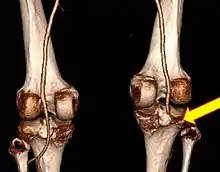

CT angiogram 3D reconstruction, posterior view showing a normal artery on the left, and occlusion to right popliteal artery as a result of a knee dislocation[10]